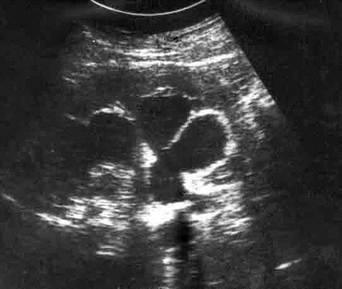

Увеличение анэхогенной зоны полостной системы (рис. ниже) свидетельствует о нарушении оттока при обтурации камнем, опухолью, сдавливании извне, рубцовом сужении или гипотонии протоков.

Сонограмма почки  (пояснения см. в тексте).